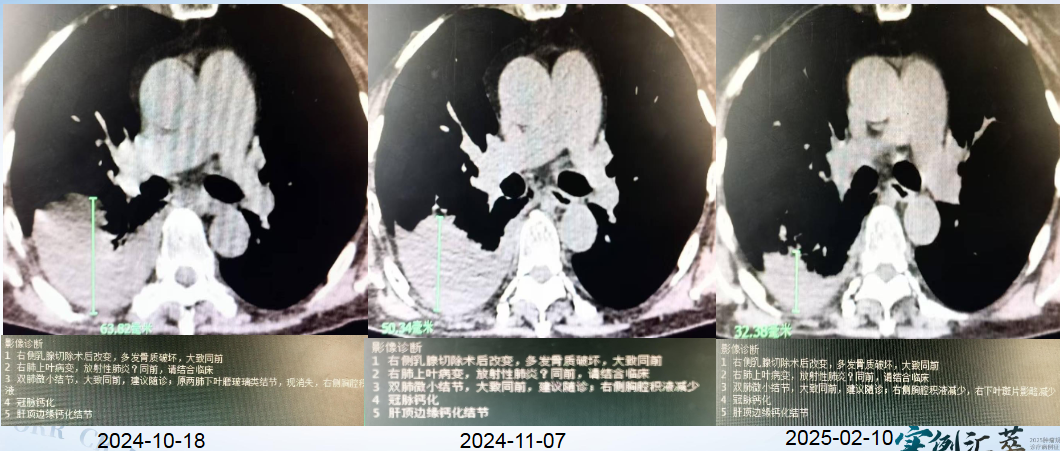

疗效:疗效评价为PR,PFS2为9个月;肿瘤标志物 CEA 从 2024 年 10 月 19 日的 43ng/ml 降至 2025 年 2 月 10 日的 16.3ng/ml,右侧胸腔积液减少。

图片7.png